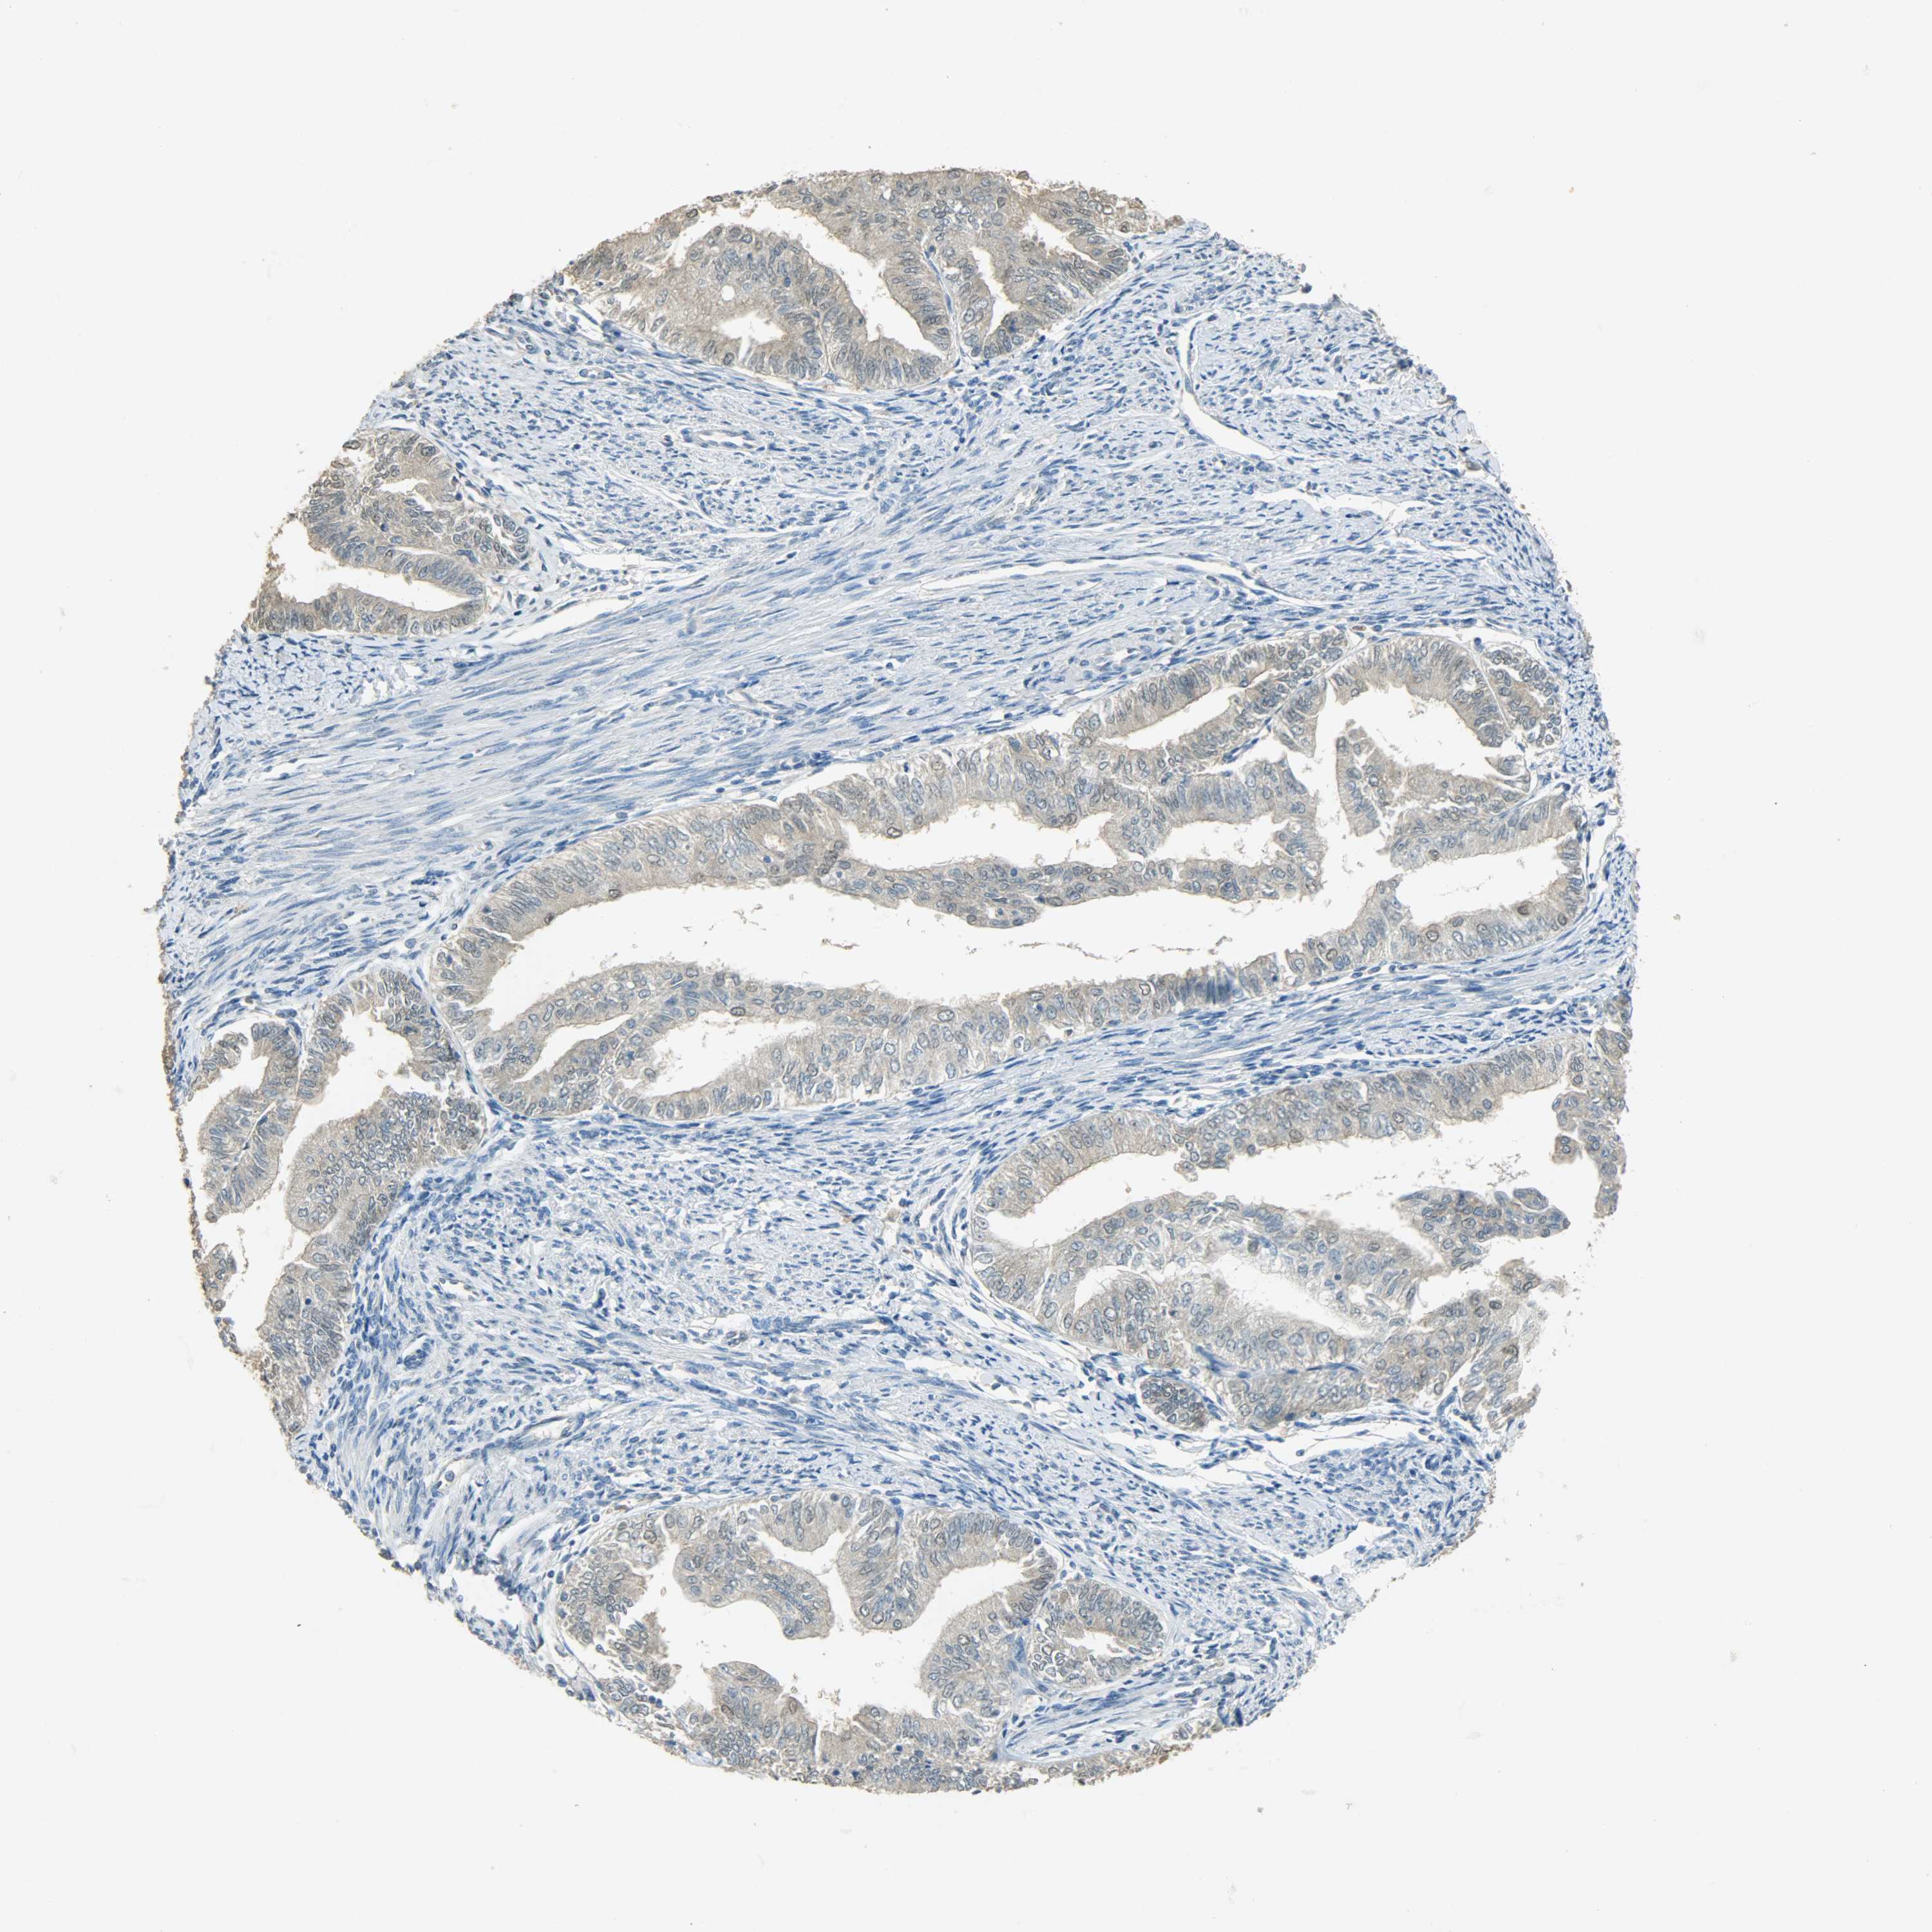

ENDOMETRIAL CANCER - Protein expressioni

A mouse-over function shows sample information and annotation data. Click on an image to view it in a full screen mode. Samples can be filtered based on level of antibody staining by selecting one or several of the following categories: high, medium, low and not detected. The assay and annotation is described here.

Note that samples used for immunohistochemistry by the Human Protein Atlas do not correspond to samples in the TCGA dataset.

Antibody stainingi

Antibody staining in the annotated cell types in the current human tissue is reported as not detected, low, medium, or high, based on conventional immunohistochemistry profiling in selected tissues. This score is based on the combination of the staining intensity and fraction of stained cells.

Each image is clickable and will lead to virtual microscopy that enables deeper exploration of all samples and also displays staining intensity scores, fraction scores and subcellular localization as well as patient and tissue information for each sample.

Antibody HPA005525

Antibody HPA064708

Antibody CAB012459

Staining

High

Medium

Low

Not detected

Intensity

Strong

Moderate

Weak

Negative

Quantity

>75%

75%-25%

<25%

None

Location

Nuclear

Cytoplasmic/membranous

Cytoplasmic/membranous,nuclear